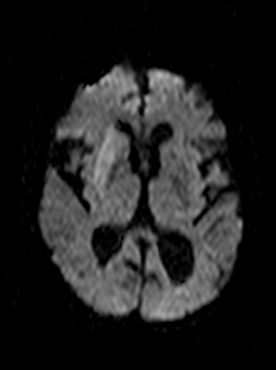

Diffusion weighted MRI (DWI) is the most sensitive method in the detection of early stroke. Diffusion weighted imaging is also able to take measurements of the movement of protons along the fiber tracts of the brain, thus enabling the visualization of cerebral white matter tracts.

CT angiographiával jól ábrázolódik az érelzáródás okozta telődési hiány MRI vizsgálattal a diffusió súlyozás (DWI) igen korán mutatja az infarctus kiterjedését.

In acute phase (12-24 hours after the occlusion of the middle cerebral artery) on CT hypodense basal ganglia, the loss of cortical white-grey matter differentiation and sulcal effacement are the characteristic imaging findings.

On MRI, diffusion restriction causes hyperintense signal on T2W images. The leptomeningeal border of the infract zone will show contrast enhancement.